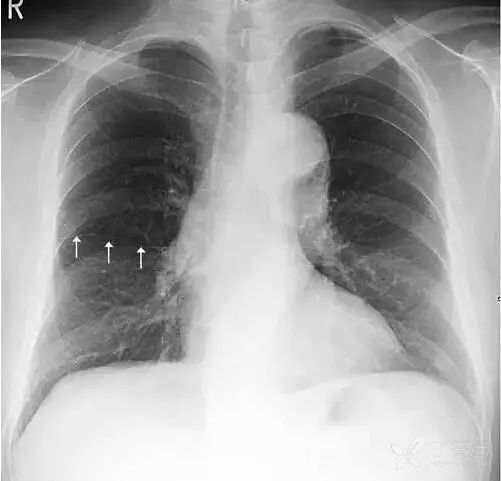

女性乳腺 女性乳腺相对胸部其他软组织较厚,因此在胸部正位X线平片上可以显示,通常重叠在两肺下野导致其密度增高,易被误认为肺内实变或肺内炎症。

上图女性乳腺影重叠在两肺下野,导致两肺下野对称性密度增高,乳腺形成投影的下缘(白色箭头)是清晰锐利的并且呈半圆形,常向外与腋部皮肤连续。没有乳腺重叠的两肺肋膈角区域更透亮。

鉴别:①两侧乳腺常规比较对称,所以在正位胸片上,乳腺重叠导致的两肺下野的密度增高也是比较对称的。而两肺下野均有病变且有分布比较对称的病理情况是比较少见的。②乳腺影的下缘清晰锐利且呈半圆形,向外与腋部皮肤连续。而肺内的病变不会延续到两肺以外。